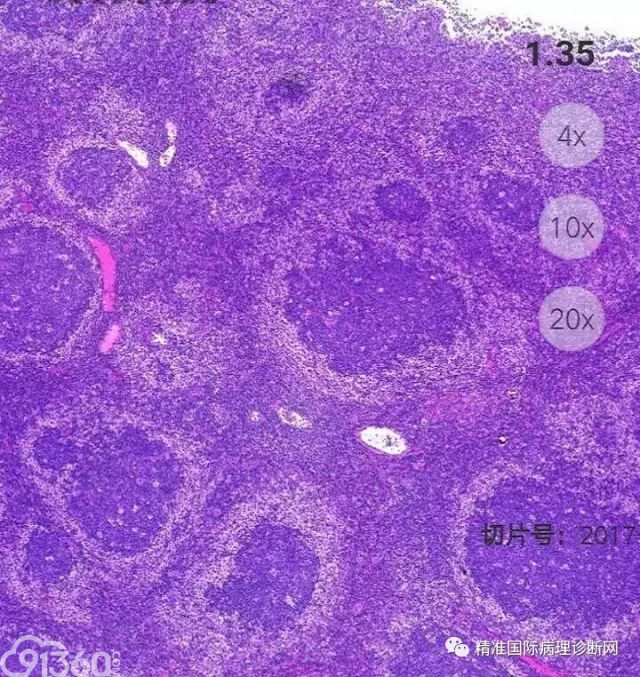

间变性大细胞淋巴瘤,ALK阳性 – 91360智慧病理网

ALK阳性间变性大细胞淋巴瘤 – 慧海拾穗博客 – 华夏病理网博客